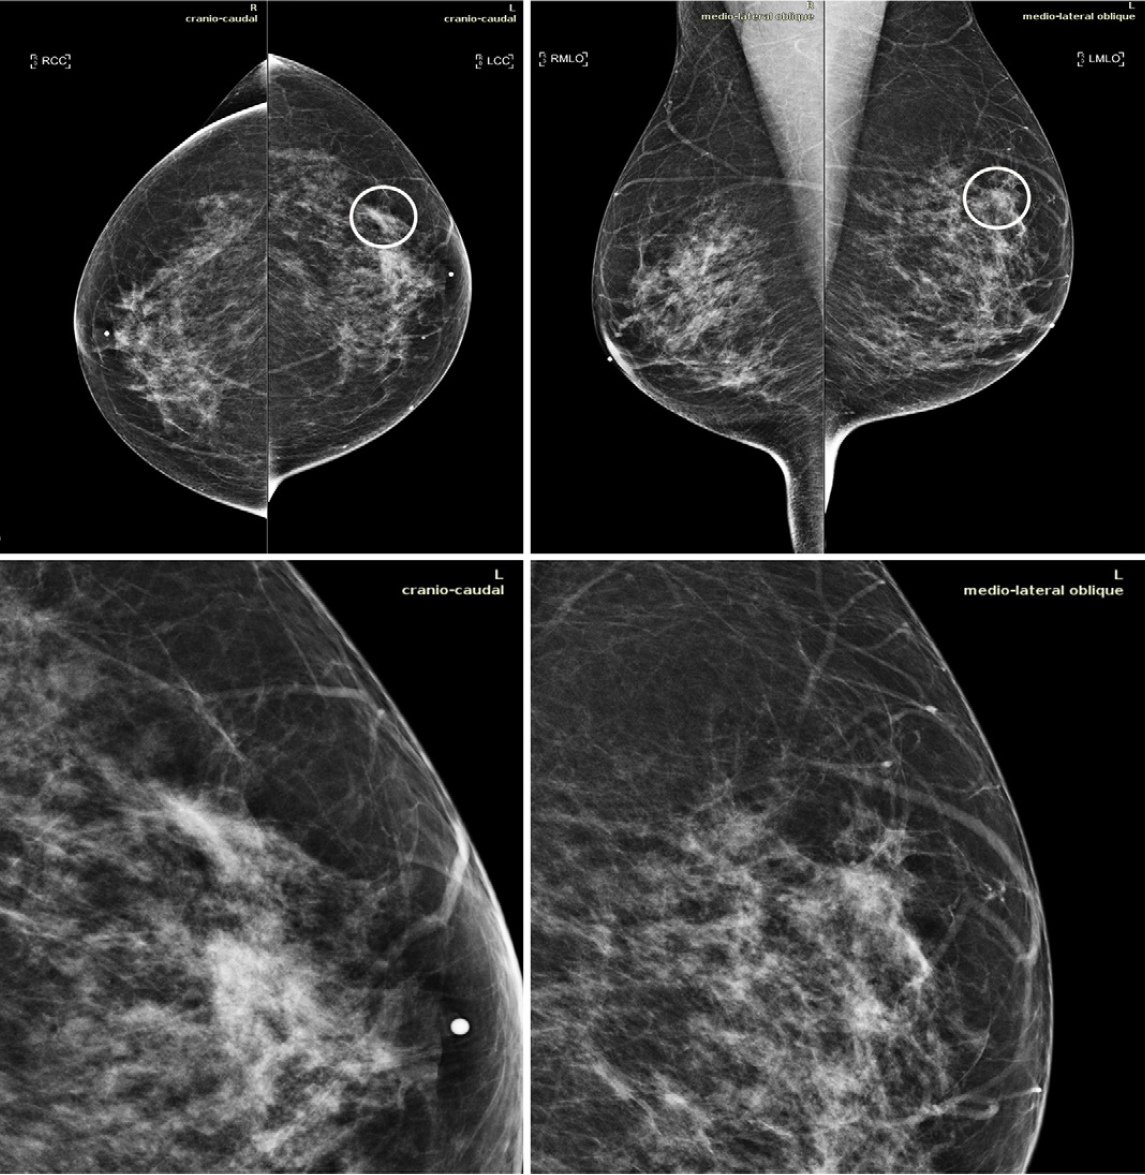

In an effort to show implementing AI does, in fact, reach those goals, Pacilè’s team tested MammoScreen™, a tool designed to identify regions suspected of having a breast cancer on 2D mammograms and evaluate their likelihood of malignancy. This system takes in the four views composing a mammogram and creates a set of imaging positions with a related suspicion score.

For this study, the team had 14 radiologists assess a dataset comprised of 240 2D digital mammography images that included a variety of abnormalities. The scans were captured between 2013 and 2016. Half were read once without AI, the team said, and the other half were twice – one without AI and once with it.